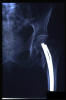

Fractura de cuello de fémur.

Fractura de cuello de fémur

Fractura de cuello de fémur con tornillos de tracción